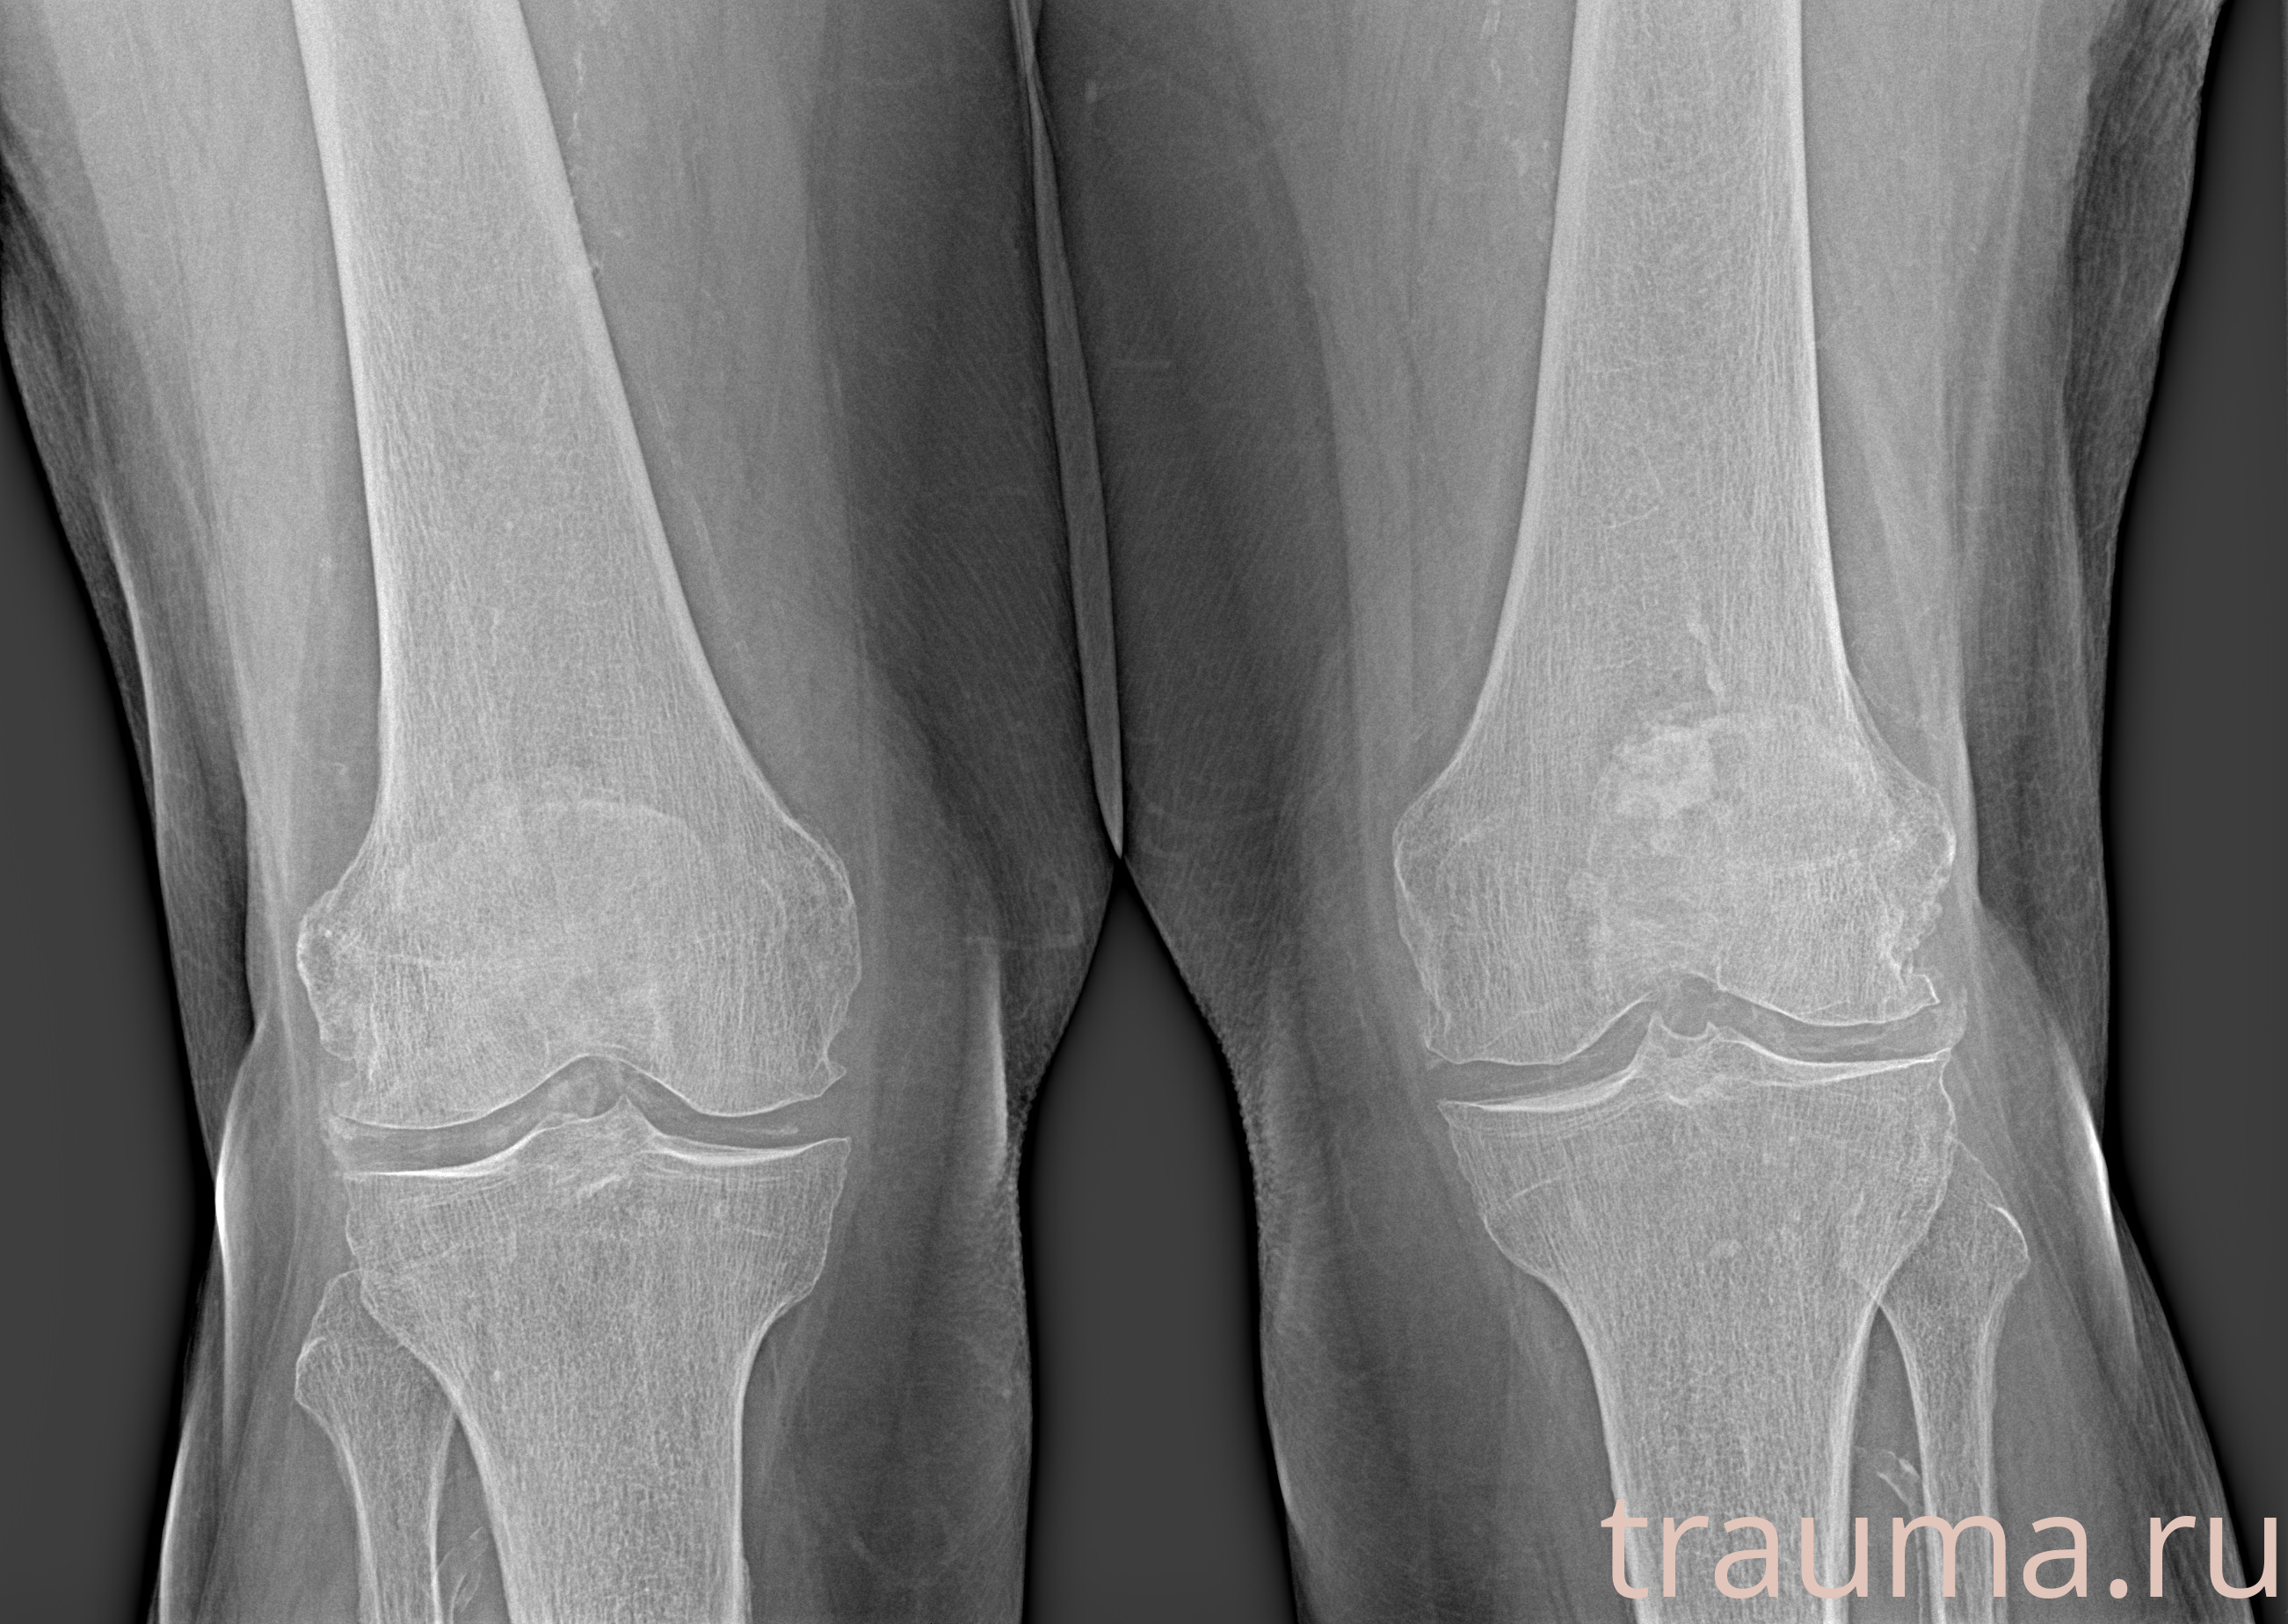

Рентген на дому: по вашему адресу приезжает врач-рентгенолог, травматолог-ортопед с мобильным рентгеновским аппаратом, проводит диагностику травмы или заболевания, делает необходимые рентгенограммы, дает рекомендации по дальнейшему лечению. Получить качественные снимки в домашних условиях возможно благодаря уникальной методике, разработанной МосРентген Центром для института  Склифосовского

при переломе шейки бедра и пневмонии от компании МосРентген Центр - партнера Института имени Склифосовского